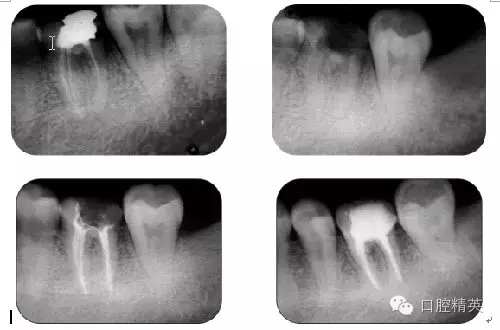

病例5:遺漏根管再治療

病例6:折斷器械取出